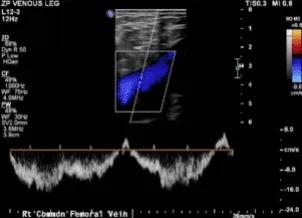

Doppler Venous Left Lower Extremity

Normal Doppler venous examination of the left lower extremity. There is no evidence of deep venous thrombosis.